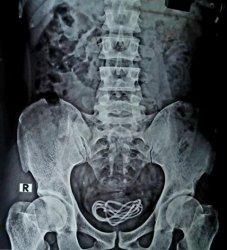

Kemudian, melalui hasil pemeriksaan rontgen, Walliul terkejut karena menemukan sebuah kabel charger yang bersarang pada kantung kemih pasien.

Foto hasil rontgen pun ia unggah di akun media sosial Facebook miliknya.